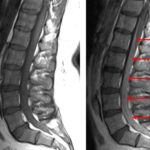

Age: 38

Sex: Male

Indication: Gradual onset bilateral leg weakness over several months

- Thickening and enhancement involving nearly all of the nerve roots of the cauda equina, most pronounced below the level of L3-L4

- Normal position, signal, and contour of the conus

- Mild multilevel degenerative changes, most advanced at L5-S1 where there is disc dessication and height loss with a broad-based disc bulge. No significant spinal canal or neural foraminal stenosis

- Chronic inflammatory demyelinating polyneuropathy (CIDP)

Thickening and enhancement involving nearly all of the nerve roots of the cauda equina, which is most consistent with chronic inflammatory demyelinating polyneuropathy (CIDP) given the reported gradual onset. Recommend correlation with CSF analysis.